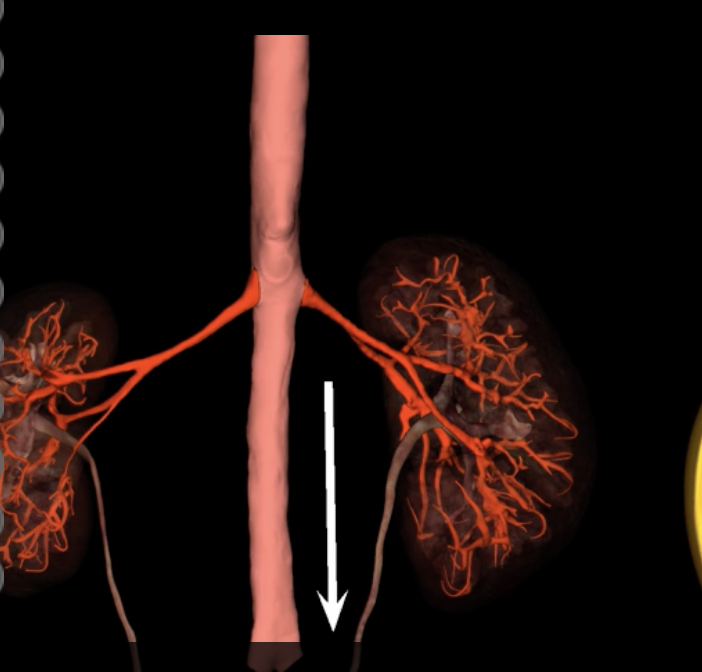

green: renal hilum

yellow: ureter

red: abdominal aorta

green yellow and red